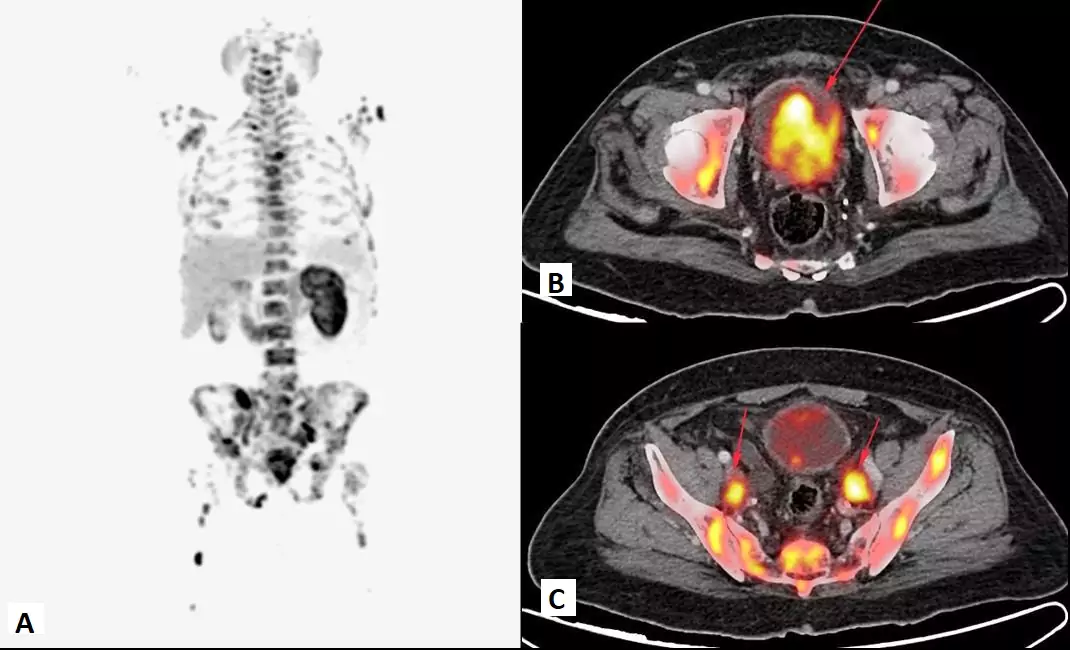

68 Ga FAPI PET/CT targets cancer associated fibroblast activation protein inhibitors. It has shown to be superior to FDG in a number of different types of cancers especially signet ring carcinoma of stomach and colon, serous adenocarcinoma of ovary, primary pancreatic cancer, biliary cancer, soft tissue sarcoma and renal cell carcinoma.